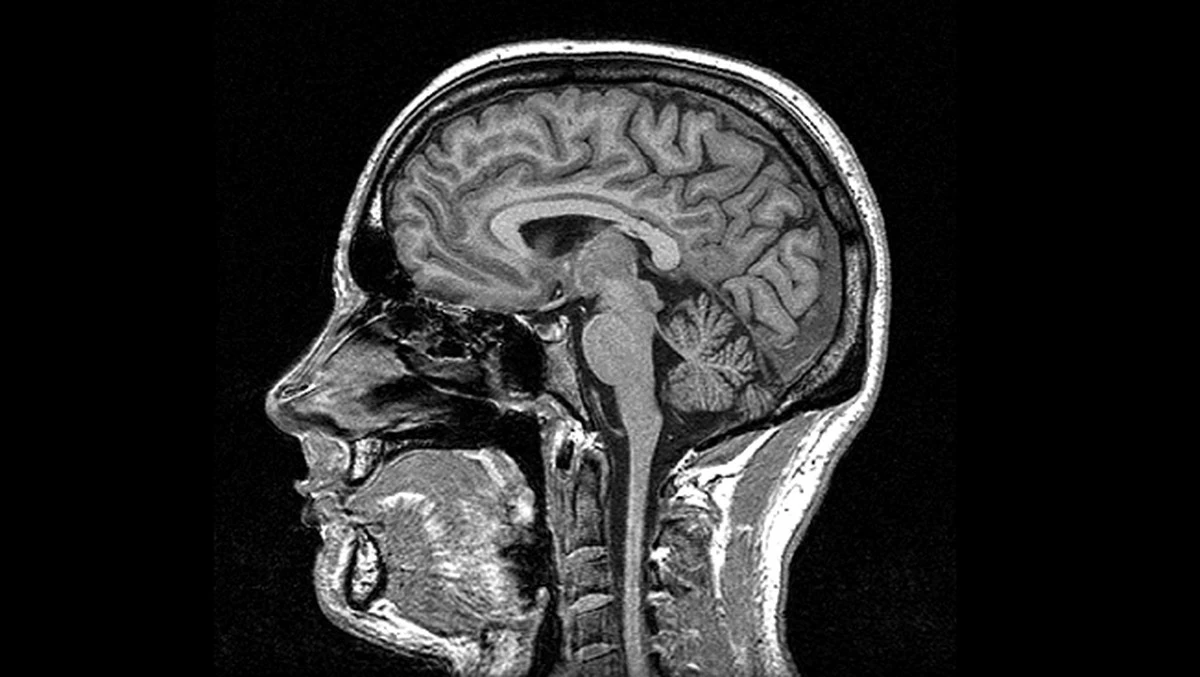

Kiedy patrzymy w stronę Międzynarodowej Stacji Kosmicznej (ISS) – którą przy dobrej pogodzie nad Warszawą czy Krakowem widać gołym okiem – rzadko myślimy o tym, co dzieje się z tkankami astronautów. Na Ziemi płyny ustrojowe są ściągane w dół. W stanie nieważkości krew i płyn mózgowo-rdzeniowy uderzają do głowy z siłą, której ewolucja nie przewidziała.

Badania opublikowane przez zespół prof. Rachael Seidler z University of Florida rzucają nowe światło na to zjawisko. Analiza skanów MRI 26 astronautów wykazała, że mózg nie tylko „puchnie”, ale fizycznie zmienia swoje położenie. Przesuwa się ku górze i do tyłu czaszki, deformując struktury, które odpowiadają za Twój ruch i czucie.

Fakt: U astronautów przebywających w kosmosie około roku, niektóre obszary w górnej części mózgu przesunęły się o ponad 2 milimetry. W ciasnej przestrzeni czaszki to dystans gigantyczny.

Mogłoby się wydawać, że 2 mm to tyle, co grubość monety 1-groszowej. Jednak wewnątrz czaszki każdy mikrometr ma znaczenie. Mózg jest otoczony płynem mózgowo-rdzeniowym, który działa jak amortyzator. W mikrograwitacji ten system zawodzi. Płyn przemieszcza się, a mózg zaczyna dryfować.

Najciekawsze jest to, że zmiany nie są symetryczne. Struktury po obu stronach mózgu przesuwają się w stronę linii środkowej. Poprzednie badania tego nie wykazywały, ponieważ naukowcy patrzyli na mózg jako na całość. Dopiero podział na 100 konkretnych regionów pozwolił dostrzec tę wewnętrzną „wędrówkę” tkanek.